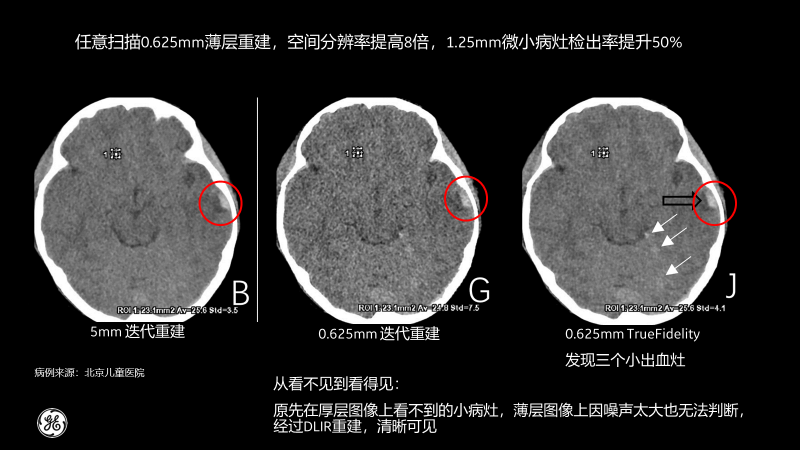

北京儿童医院的测试病例也显示,经过TrueFidelity,任意扫描0.625mm薄层重建,空间分辨率能提高8倍,1.25mm微小病灶检出率提升50%,最终额外发现了3个之前看不到的微小病灶。

相比传统CT图像对腹部检查一般都选择5mm厚层重建,TrueFidelity可对任意体型任意部位的检查进行0.625mm的薄层图像重建,真实还原图像的解剖细节和纹理,提高微小病灶的发现几率,有助于早诊早治,极大提高医生的诊断信心。

尤其是对于天然对比度低的组织结构,比如腹部成像,TrueFidelity的诊断优势尤为明显,并为临床诊断带来了显著突破。